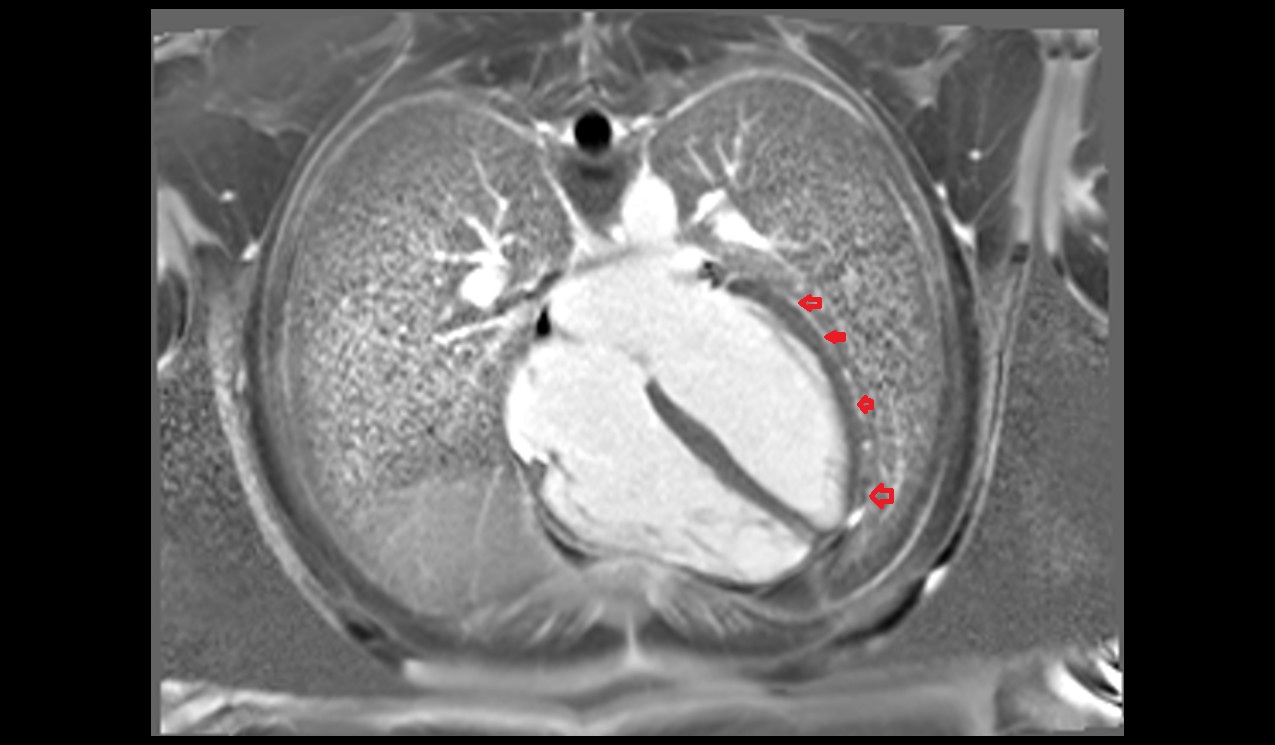

- Pericardium

- Heart

- Myocardium

- Endocardium

- Epicardium

- Pericardial cavity